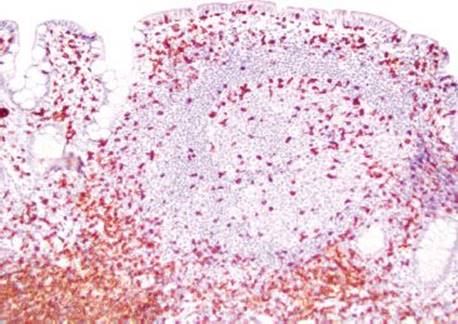

Answer: You are not alone! Prominent lymphoid aggregates can be especially alarming in the terminal ileum and, thus, are a common source of consultation. The small bowel serves as an essential component of the immune system through its perpetual surveillance of the passing luminal contents. Diligent immunosurveillance is facilitated through specialized epithelial cells (M-cells) that transport luminal antigens to the lymphoid aggregates (designated “Peyer patches” when seen in the terminal ileum). Hyperplastic lymphoid aggregates can be sufficiently large as to be visualized endoscopically and can also serve as intussusception lead points, especially in young children.5,6 The epicenter of lymphoid aggregates is in the mucosa but especially prominent cases can feature extension into the submucosa, raising concerns for a hematolymphoid malignancy. Histologic features reassuring for a benign, reactive process include the presence of germinal centers, tingible body macrophages, and a polymorphous constituent lymphoid population (i.e., a variety of cell sizes represented); however if the focus in question seems at all concerning, a quick immunohistochemical panel may be worthwhile (Figs. 3.19–3.37) (Table 3.1).

Figure 3.21 Normal terminal ileum. As this case illustrates, large lymphoid aggregates can occasionally extend below the muscularis mucosae (bracket) into the submucosa. Features in support of a benign process include variably sized lymphoid aggregates, germinal centers (arcs), tingible body macrophages (macrophages containing apoptotic debris in the cytoplasm, arrowheads), and a polymorphous lymphoid population (variably sized lymphocytes, best seen at high-power, Figures 3.29–3.30).

Figure 3.22 Normal terminal ileum. Note how the overlying epithelium could be theoretically “peeled” off the lymphoid aggregates since the large lymphoid aggregates are seen gently pushing aside the epithelium and not associated with active chronic inflammatory injury. Note the features of benignity: variably-sized lymphoid aggregates, germinal centers, and tingible body macrophages.

Figure 3.23 Normal terminal ileum. With such large prominent aggregates, the ever so slight scattered appearance to the crypts is entirely within the spectrum of normal terminal ileum architecture. Note that the overlying epithelium could be theoretically “peeled” off the lymphoid aggregates since there is no active chronic inflammatory injury linking the lymphoid aggregates to the epithelium.

Figure 3.24 Normal terminal ileum with variably sized lymphoid aggregates, germinal centers, and tingible body macrophages.

Figure 3.25 Normal terminal ileum. Crushed lymphoid tissue traversing the muscularis mucosae can raise concerns for a malignant hematolymphoid process (bracket). In this case, however, the intact lymphoid aggregate shows germinal centers (arc), tingible body macrophages (arrowheads), and a polymorphous lymphoid population, all features of a benign lymphoid process.